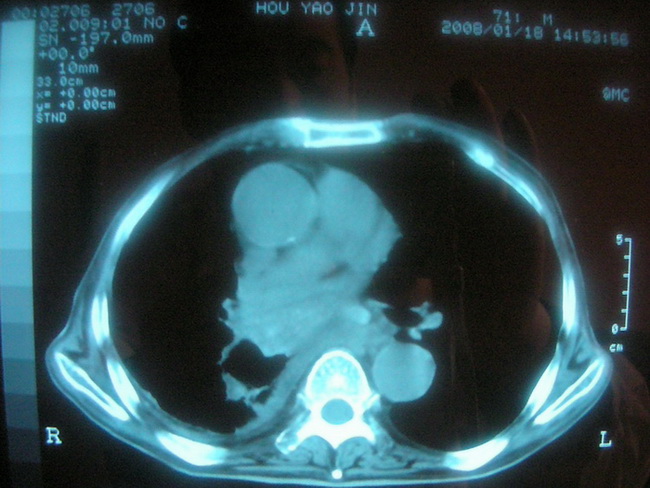

以下是引用卜一在2008-2-16 6:10:00的发言:[br]右肾增大,实质内明显见占位性病灶,并突出体外,密度不均匀。另双肺上叶见散在的斑片 索条及点状结节样致密影,右下肺门区不规则团块,右侧胸腔积液并形成局限性气胸。考虑:1 右肾癌。2 右肺门淋巴结转移及肺内 胸膜转移。3 右上肺陈旧结核。

以下是引用zjzjr在2008-2-16 14:15:00的发言:[br]1 右肾癌伴 右肺门淋巴结转移及肺内 胸膜转移。2右侧胸腔积液引流后改变(可见引流管影)3 双上肺继发型结核。